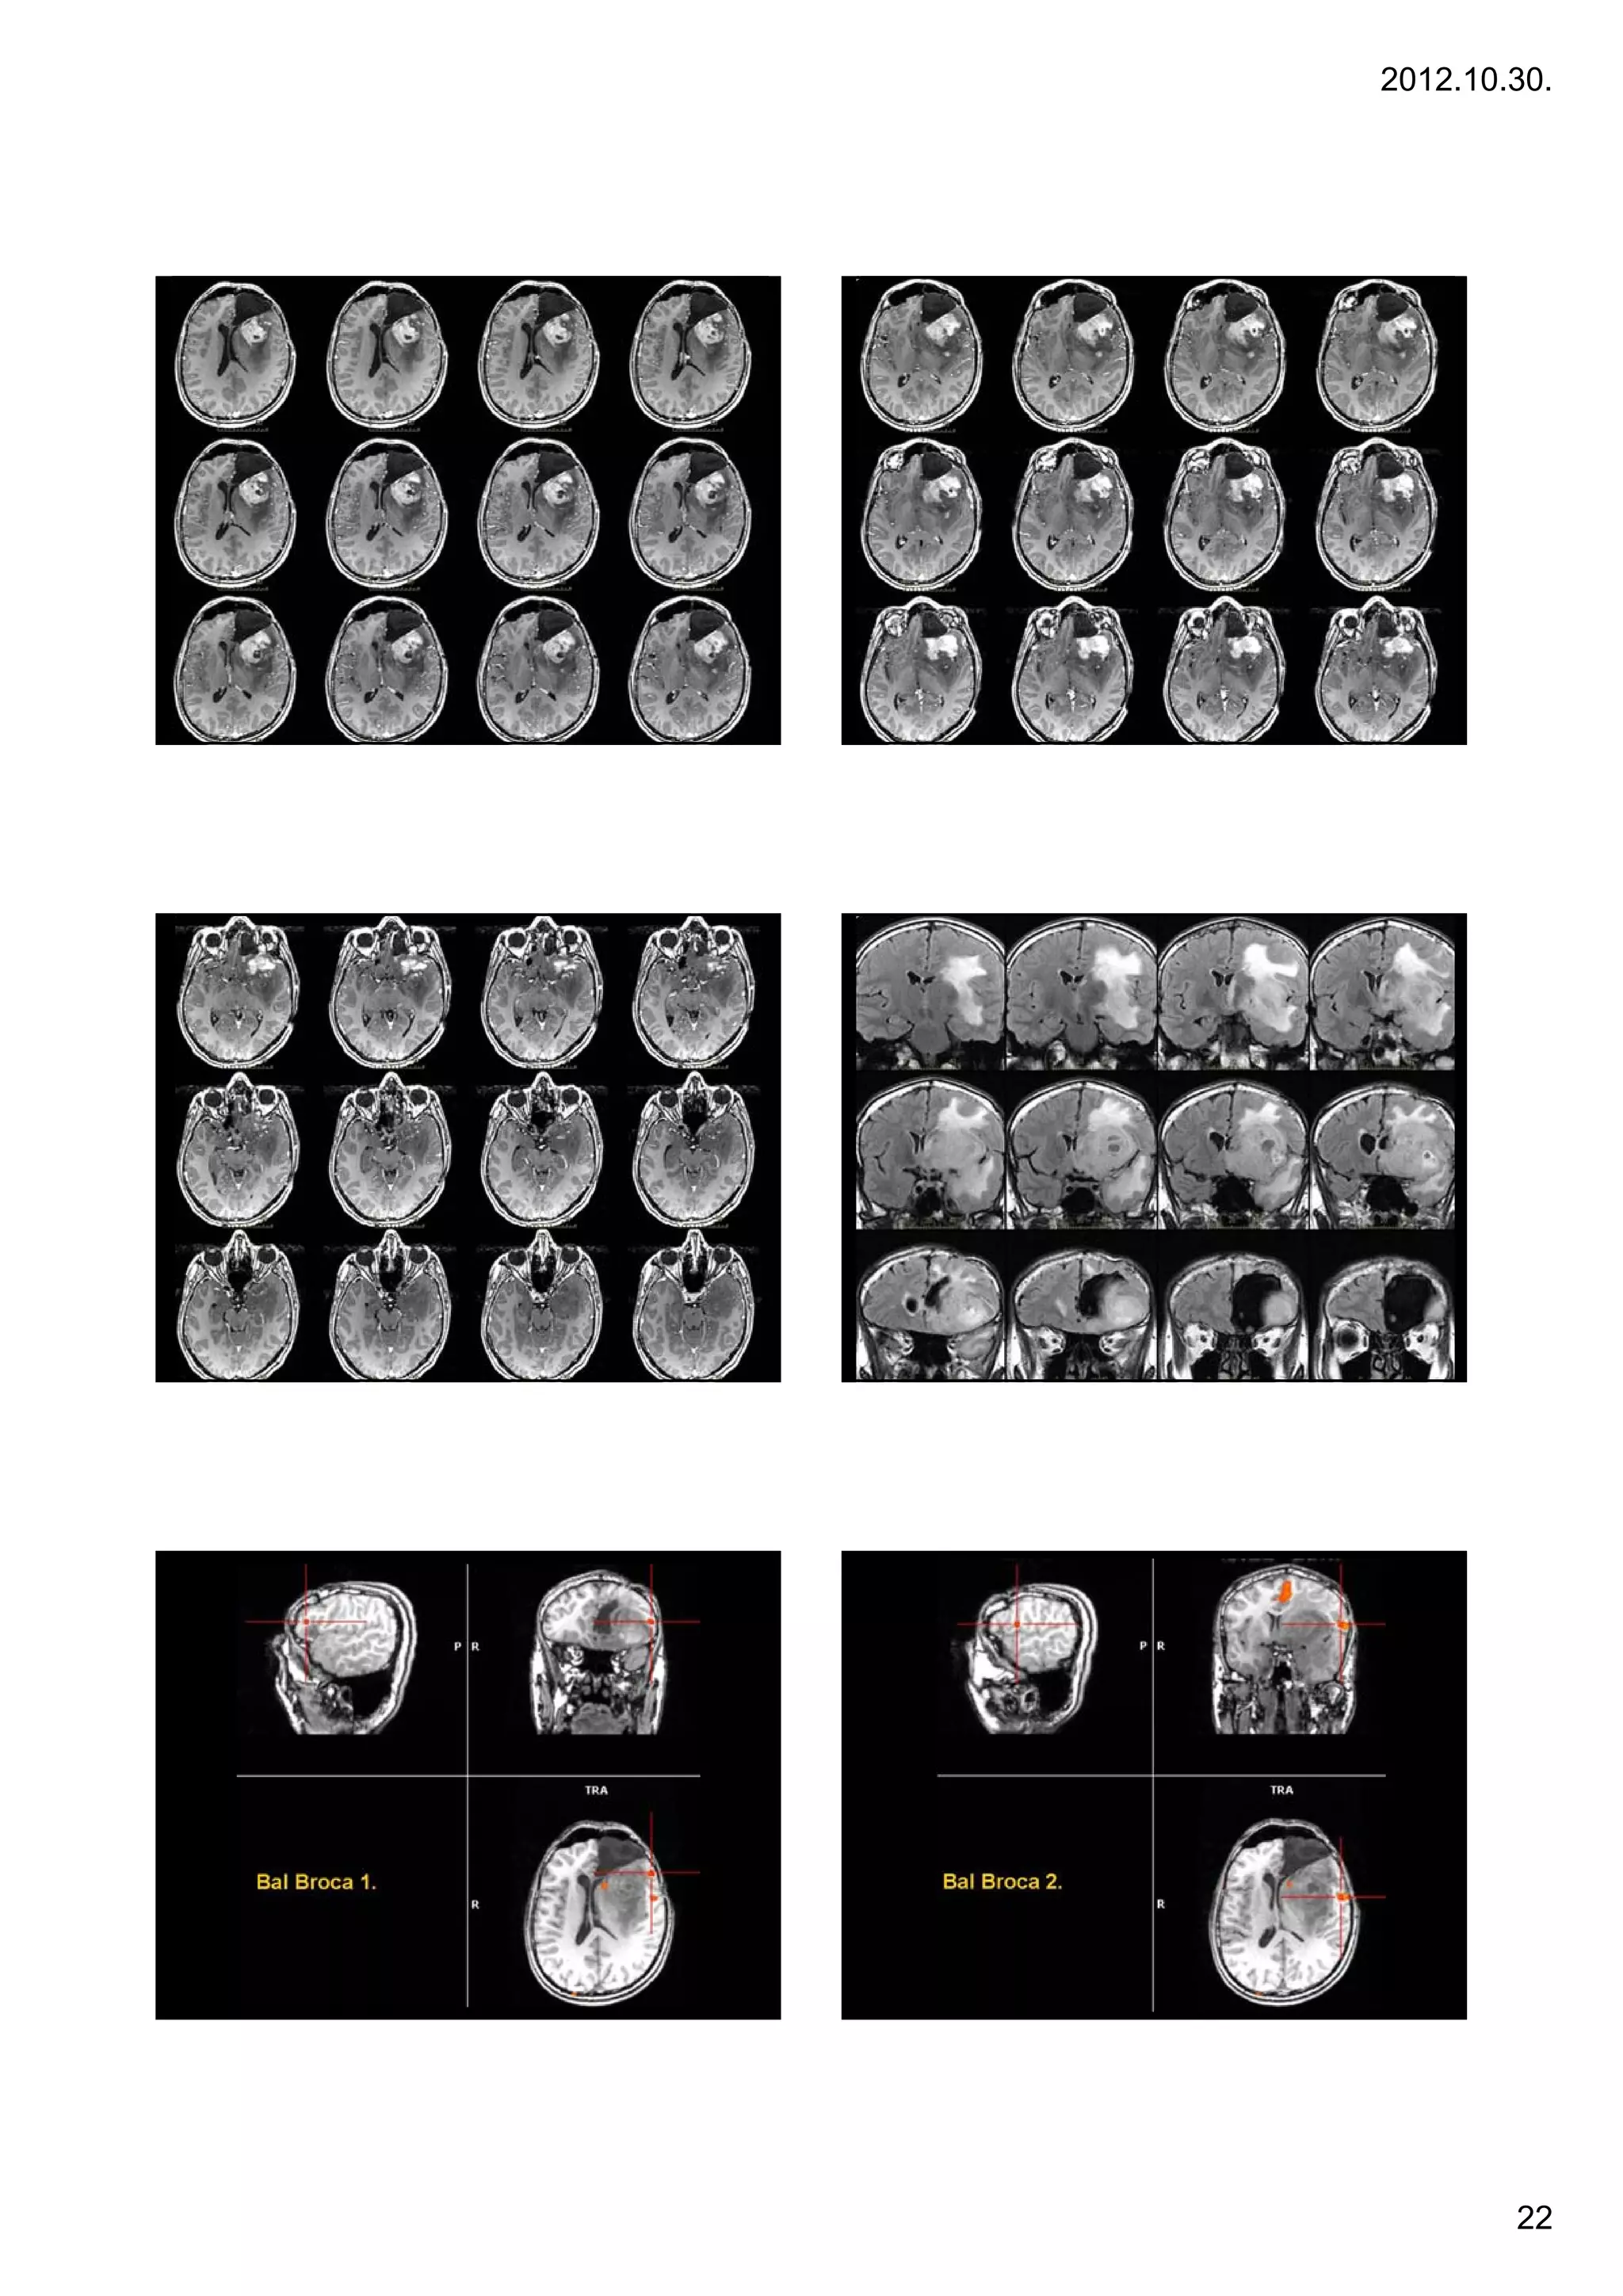

Case 4

4.

21

22

Low grade gliomas

Gliomas are named according to the specific type of cell they share histological

features with, but not necessarily originate from. The main types of gliomas are:

Ependymomas — ependymal cells.

Astrocytomas — astrocytes (glioblastoma multiforme is the most common

astrocytoma).

Oligodendrogliomas — oligodendrocytes.

Case 5

5.   Mixed gliomas, such as oligoastrocytomas, contain cells from different types of

glia.

g       ,           g        y       ,                            yp

Gliomas are further categorized according to their grade, which is determined

by pathologic evaluation of the tumor.

Low-grade gliomas [WHO grade II] are well-differentiated (not anaplastic);

these are not benign but still portend a better prognosis for the patient.

High-grade [WHO grade III-IV] gliomas are undifferentiated or anaplastic; these

are malignant and carry a worse prognosis.